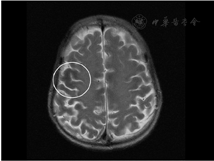

影像学检查:头颅MRI(图2)提示双侧额颞顶枕叶皮质下及基底节区低信号,考虑代谢性脑病可能。腹部MRI(图3)提示肝实质和胰腺T1WI及T2WI+FS信号弥漫性减低,均呈极低信号。腹部超声提示肝脏轻度纤维化、肝左叶体积增大,脾轻度肿大,胰腺萎缩伴纤维化、双肾体积缩小、前列腺体积缩小。睾丸超声提示双侧睾丸萎缩。骨密度提示左侧股骨颈骨密度(bone mineral density, BMD)测量值符合骨质疏松(腰椎L1-4 BMD为0.879 g/cm2,T值-1.7,Z值-0.5;左股骨颈BMD为0.638 g/cm2,T值-2.6,Z值-1.2;左股骨上端为0.731 g/cm2,T值为-2.0,Z值为-1.4)。心电图示窦性心动过缓、异常"Q"波。

注:白色圈内:颞叶低信号区

临床上血色病通常因实验室检查提示血清铁蛋白或转铁蛋白饱和度升高而发现,但上述两项指标特异性较低,往往需要进一步检查来明确诊断[2]。影像学是诊断血色病的重要辅助检查,当肝脏、脾脏和胰腺等脏器出现铁超载时,因铁的超顺磁性效应,MRI-T2加权序列可表现出明显低信号[3]。若肝实质内铁含量>7 mg/g肝重量时,MRI-T2序列图像可出现"黑肝症",这对量化和可视化血色病患者肝脏铁含量具有重要意义[4]。本例患者MRI-T2序列可见肝实质信号弥漫性减低,表现为明显"黑肝症",除此之外胰腺和双侧额颞顶枕叶皮质下及基底节区也出现信号缺失,提示本例患者肝脏、胰腺,甚至是脑部均可能存在铁超载。